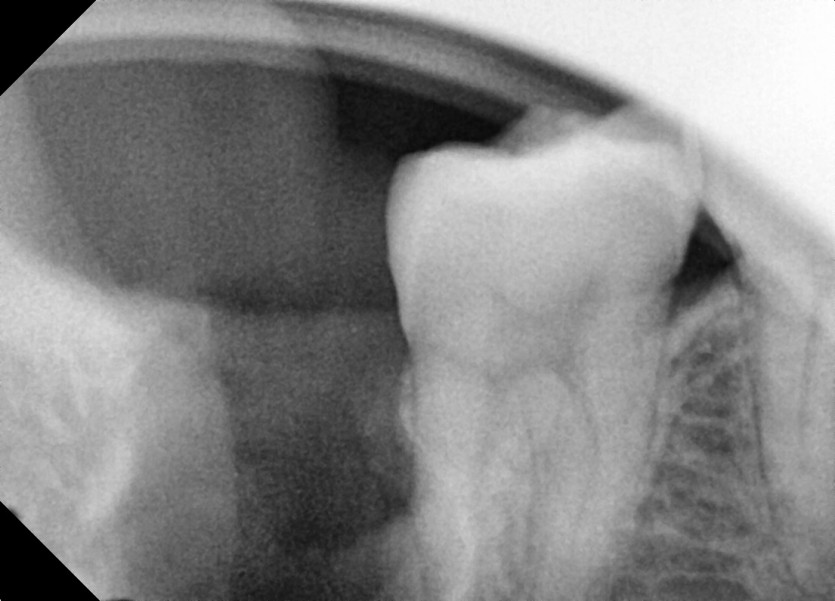

#18,48 사랑니 발치

구강외과 전문의가 당일발치했습니다.